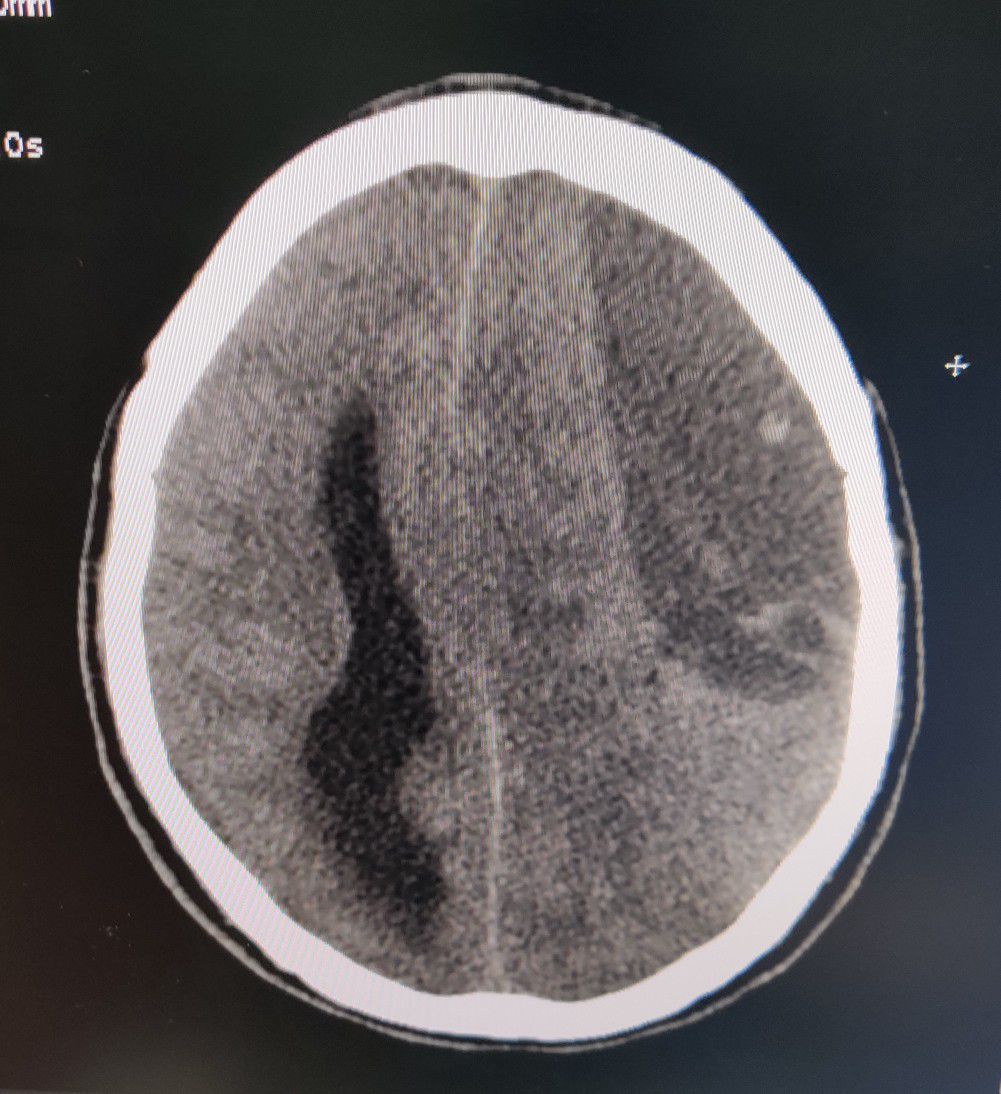

Ischemic CVA or Epidural Hematoma ?

Brain

Ischemia

Epiduralhematoma